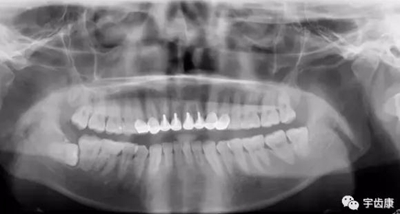

X線閱片知識